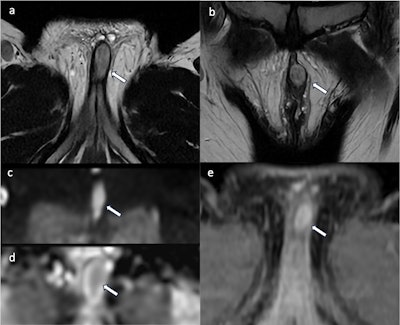

A 37-year-old woman presented with a nodule above the clitoris that was slow-growing for 10 years but which had recently become painful. Axial (a) and coronal (b) T2WI show an oval, well-defined vulvar mass (white arrow) involving the clitoral glans without invasion of adjacent organs with a hyperintense, heterogeneous signal. The lesion presents diffusion restriction on DWI (c) and the corresponding ADC map (d). Axial contrast-enhanced axial fat-saturated T1WI shows heterogeneous enhancement (e). The lesion was removed surgically, and the final diagnosis was schwannoma. All images courtesy of Drs. P. Clauser, M. Dolciami, B. Gui et al and EJR.